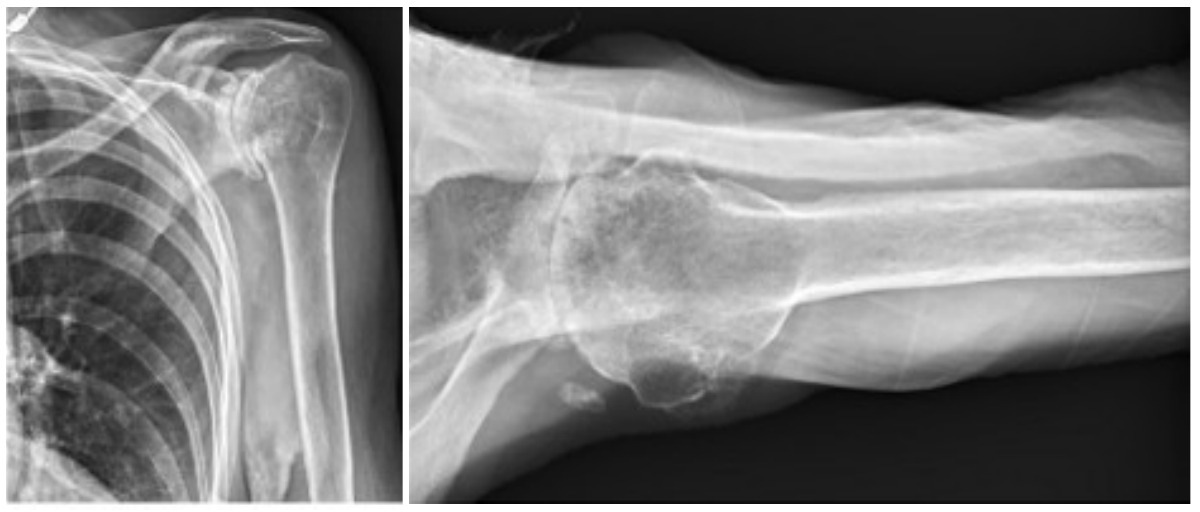

Case three is a 79-year-old male with cuff tear arthropathy with significant bone loss and medialization of his joint line (Figure 9). Three-dimensional imaging confirms these findings (Video 1). Due to the loss of posterior bone and available bone down the native glenoid vault, alternative center line was selected for this patient. Post-operative radiographs show a glenoid baseplate with exaggerated inferior tilt and anteversion, consistent with utilization of the alternative center line (Figure 10).

Case four is a 63-year-old retired nurse who was very active with weight lifting, horseback riding, tenis, and yoga. Surgical history included two prior arthroscopid debridements and capsular release. His pre-operative Subjective Shoulder Value (SSV) was 30% and pain score was 10/10. Exam showed 140° of active forward flexion, 30° of active external rotation, and active internal rotation to the sacrum. Radiographs (Figure 11) and CT (Figure 12) scan showed end stage arthritic changes without significant glenoid deformity. Options were discussed with the patient and due to his relatively young age and activity level, an inlay glenoid component was selected. This was combined with mild high side reaming. Radiographs at one year show a well seated component without signs of loosening or failure (Figure 13). Postoperative SSV was 95% and he returned to all prior activities (Figure 14).